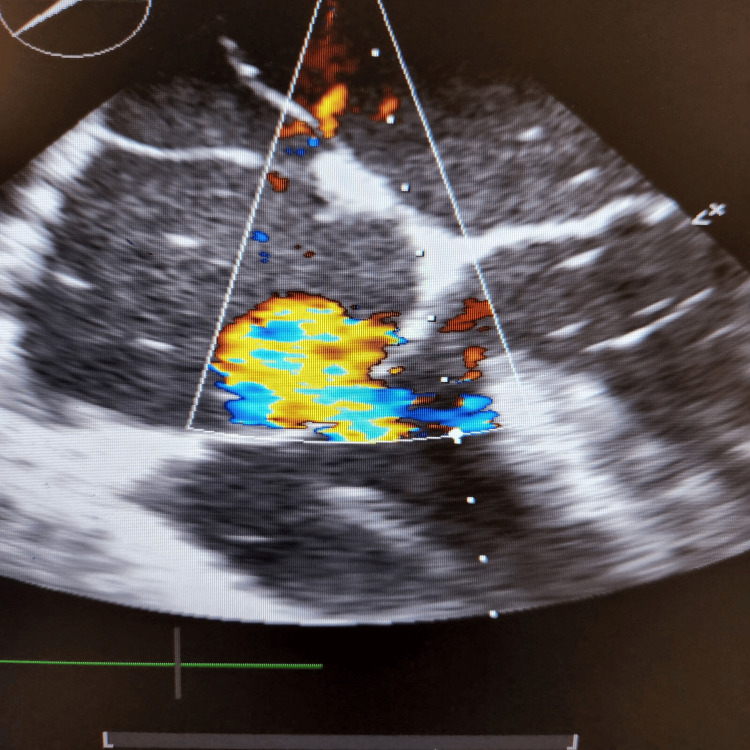

During the final stages of the ERCP procedure, a significant decrease in oxygen saturation and the emergence of irregular heartbeats were noticed. An intraoperative trans-esophageal echocardiogram (echo) revealed numerous air pockets in the right atrium, right ventricle, and left ventricle. Importantly, a patent foramen ovale was detected as shown in Figure 2, with indications of air bubbles (seen as white spots on 2D echo) passing through it into the left side of the heart as seen in Figures 3, 4. The patient was intubated in response to decreased oxygen levels while still in the operating room.

Gas embolism during ERCP is a rare but potentially fatal complication. It occurs when air enters the systemic circulation, leading to cardiovascular and pulmonary complications. One possible mechanism of gas embolism during ERCP is the intramural dissection of insufflated air into the portal venous system during endoscopic sphincterotomy [ref. 5]. In the presented case, the presence of a patent foramen ovale allowed for the passage of air bubbles from the right side of the heart to the left side, leading to systemic circulation and causing cardiovascular complications [ref. 2]. The patient’s case is unique because it involves a cardiac air embolism leading to difficulties during ERCP, which is an uncommon complication. The presence of a patent foramen ovale further complicates the situation, as it allows for the passage of air bubbles into the left side of the heart, increasing the risk of systemic complications.